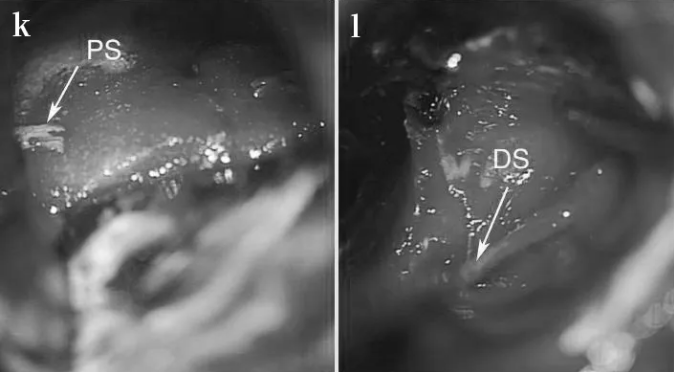

STEP 06:重建近端(k)和远端(l)神经残端(PS近端残端,DS远端残端)